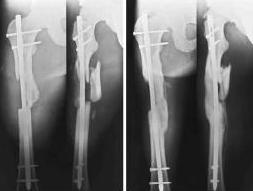

15.09 проведено оперативное лечение (Блокирующий стержень левого

бедра - статическая система. Открытое вправление вывиха в суставе

Лисфранка и фиксация мет. фиксаторами.)

1. По бедру... Стержень конечно тонковат, торчит в колено..не совсем ясно, что там с прокстимальным блоком(... Если не будет нагрузки, получите замедленное стащение, потом когда датите нагрузку получите перелом винтов (в лучшем случае), штифта - в худшем(

То, что перелом распространяется на сустав не имеет никакого значения и влияния (в данном конкретном примере) для отсрочки динамизации и нагрузки.

>>>Стержень конечно тонковат, торчит в колено...

Видимо не просто так он торчит, а его специально не добили, чтобы мыщелки "зацепить" на обе стяжки.

А вот если дать раннюю нагрузку на мыщелковые переломы бедра, может случится беда.

>>>Просто перештифтуйте ЗАКРЫТО более массивным штифтом, с рассверливанием и заблокируйте динамично.

А вот это до полной консолидации мыщелков сложновато. надо сначала влезть в коленный сустав, удалить гвоздь, выполнить ретроградное рассверливание и введение толстого штифта, не развалив при этом мыщелки. Коленка может "обидиться" на повоторное штифтование. Если штифтовать антеградно опять возникает вопрос: надо ли предварительно фиксировать мыщелки винтами?